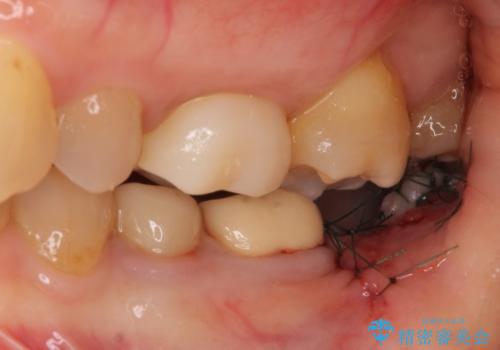

- 抜歯が必要と診断された奥歯の治療を希望して来院された患者様です。

一番奥の歯は歯根の一部を残した状態で、手前の歯とブリッジが装着されていました。

奥歯は歯根周辺の歯槽骨が広範囲に失われており、抜歯が必要と判断されました。

ブリッジの手前側の歯は、根管治療が必要な状態でした。

手前は根管治療後に補綴治療を、奥は骨造成後にインプラント埋入し、手前の歯と同時に補綴治療を行うこととしました。